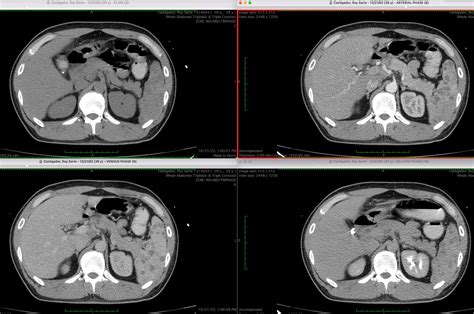

• Imaging Tests: CT scans and ultrasounds are commonly used to visualize the stones and assess their size and location.